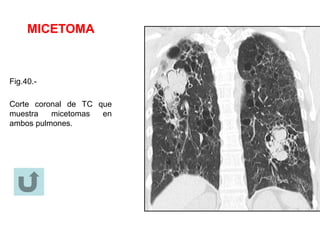

MICETOMA

Estudio con Rx y TC.-

Un micetoma puede moverse a una localización dependiente cuando el

paciente cambia de posición, y puede mostrar un signo de la media luna

(fig.40). Los cortes de TC pueden mostrar un patrón tipo esponja y focos

de calcificación. Un sinónimo es “bola de hongos” (ver también signo de

la media luna).

Fig.40.-

Corte coronal de TC que

muestra micetomas en

ambos pulmones.